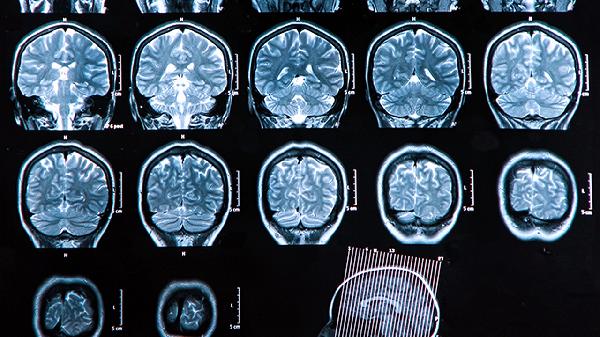

锻炼大脑的思维能力,可以通过一些方法来实现,比如进行认知训练、学习新技能、参与社交活动、坚持体育锻炼以及尝试冥想放松等。这些方式都能有效促进大脑的神经可塑性,而提升思维能力需要多方面的刺激和长期的坚持。